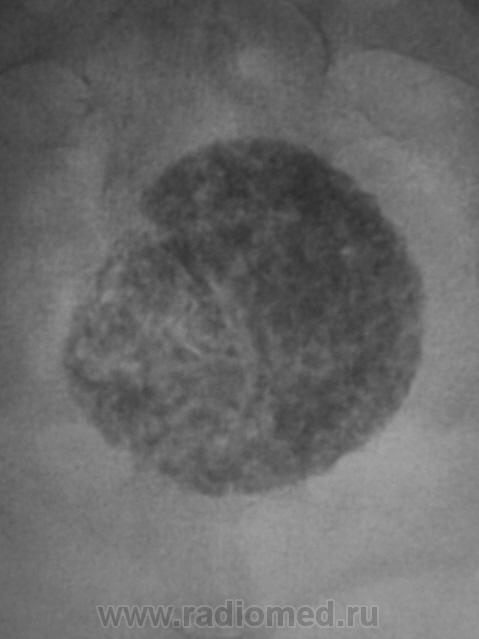

Пациентка направлена на рентгенографию тазобедренного сустава по поводу "артроза". Беспокоят вроде-бы боли в области правого тазобедренного сустава. Произведена рентгенография в прямой стандартной проекции. Рентгенологических данных за артроз не было. Но по краю пленки что-то "маячило". Пациентке 56 лет.

Досняли... Ваше мнение уважаемые коллеги?

Или конкремент мочевого пузыря или фиброматозный узел с обызвествлением. Если в больнице есть УЗИ.... нет - экскреторная, до нее можно латерограмму, пневмоцистограмму и т.п.

Добрый вечер, Валентин Львович! Представленный Вами случай - обызвествление миомы матки, раза три наблюдал. Неплохо бы боковую проекцию, вдруг хондрома крестца.

Вообще-то весьма характерная картина фибромиомы матки, осмотра гинеколога и УЗИ вполне достаточно

Согласен, и даже без каких-либо минимальных возражений